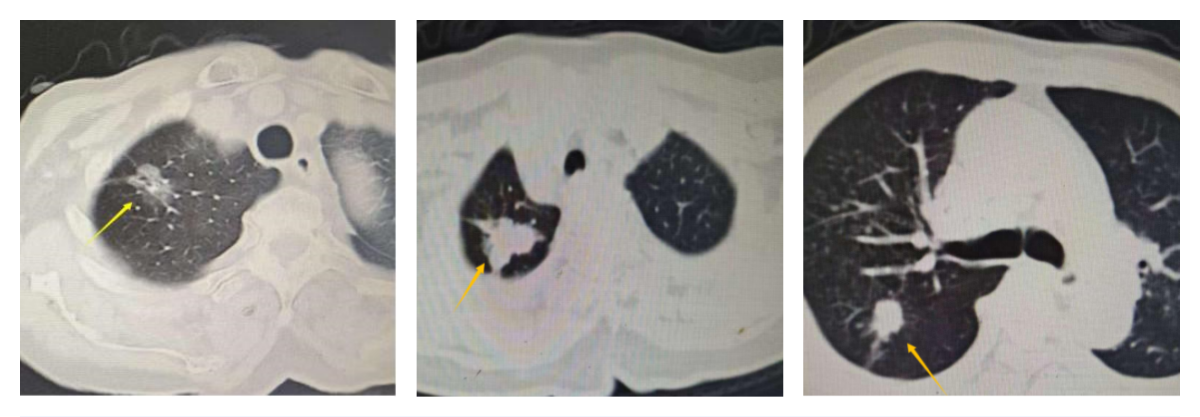

这三位高龄患者——贺奶奶(87岁)、肖奶奶(80岁)和李爷爷(82岁),均因体检发现肺部结节,高度怀疑为早期肺癌。面对癌症诊断和患者的高龄状况,家属们一度陷入对传统手术风险的深深忧虑,治疗之路仿佛蒙上了一层阴霾。

手术的成功,离不开团队的精诚协作。在精细的麻醉管理与优质的围手术期护理护航下,团队凭借精湛的技术与丰富的经验,仅通过约3厘米的微小切口,便精准、安全地完成了肺癌根治术。术后病理结果证实了术前诊断,三位老人都获得了根治性治疗。